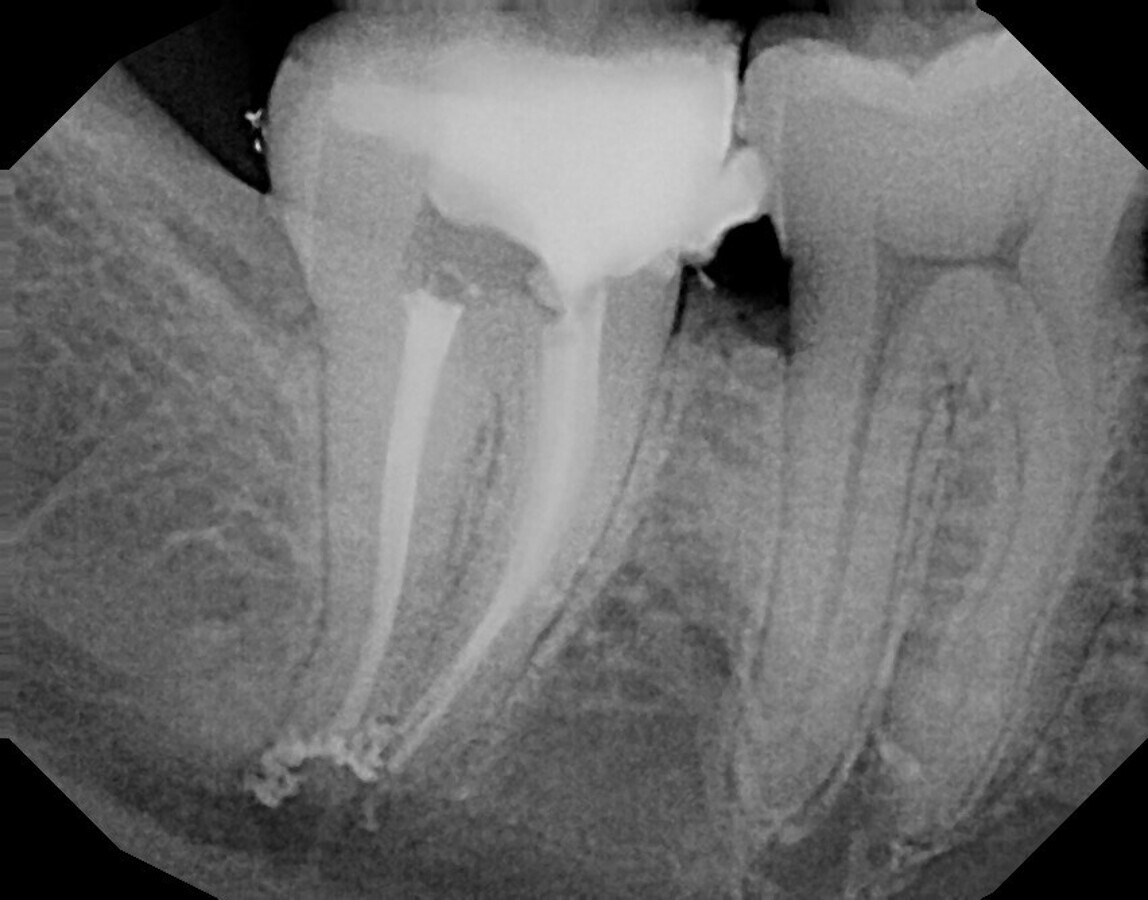

Fig. 1: Pre-op radiographic image of tooth #47.

This spring, a 33-year-old patient was referred to our practice complaining of pain in the right lower jaw. Radiographic diagnostics revealed, among other things, that the root canals were longer than usual. The mesial canals were 23 mm long, and the distal canal 22 mm. In addition, the canals were clearly narrowed in the apical third. Successful navigation through the root canal system would therefore become particularly difficult. Tooth #47 also showed a conspicuous brightening in the radiographic image (Fig. 1). The diagnosis was necrosis with asymptomatic periapical periodontitis. The patient agreed to the necessary root canal therapy.